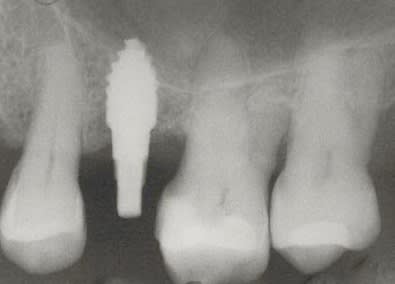

> Voici le cas en image

> Mon doute portait donc sur la face vestibulaire de l'implant en place de 43.

>

> Implant4.5*11 Astra

Serrage manuel, sans lambeau. Extraction implantation immédiate

le 4.5*11 me semblait convenable. J'avais peur que si je metais du 4*11 l'espace entre les cretes vestibulaires et l'implant allait creer une recession si je ne comblait pas ce vide

Rappelons qu'en mesurant j'ai 1.25 mm d'os au final et pas 0.5-0.8mm